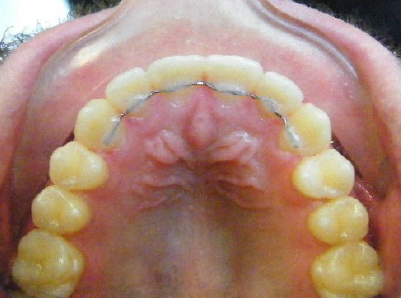

Patient 1: Severe upper and lower crowding with congenitally missing two lower adult teeth and a crossbite.